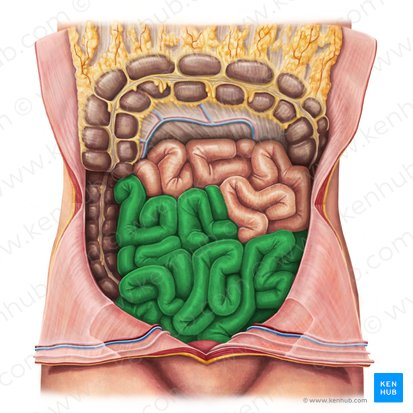

Small intestine / colon

the part of the digestive tract located between the stomach and the large intestine, where most of the digestion and absorption of nutrients occurs.

Jejunum

This is the middle section of the small intestine, and is characterized by numerous folds and villi, which increase the surface area for nutrient absorption.

Most of the absorption of carbohydrates, lipids, and proteins occurs

Ileum

The final and longest section of the small intestine, which controls the passage of material into the large intestine.

primarily absorbs vitamin B12, bile salts, and any remaining nutrients, and also plays a role in the transport of water and electrolytes.

Large intestine / colon

the final section of the digestive tract, responsible for absorbing water and electrolytes and forming feces.

Jejunum

The middle section of the small intestine, where most of the digestion and absorption of carbohydrates, lipids, and proteins occurs.